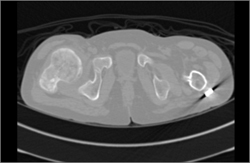

Diagnosis

Myeloma